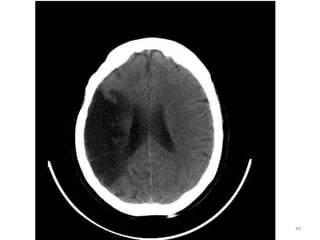

1. Corno Anterior do

Ventrículo lateral D.

2. Corpo caloso D.

3. Terceiro ventrículo.

4. Plexo coróide.